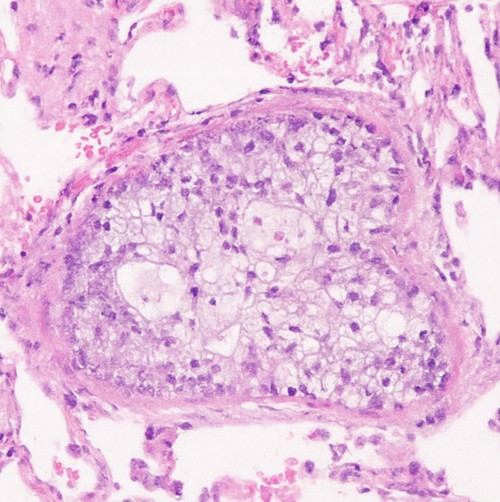

Histologie

• Nachweis atypischer, vitaler Tumorzellverbände in Gefäßlumina (oft mit Kernatypien, erhöhter Mitoseaktivität).

• Oft assoziiert mit Fibrin, Thrombozyten, Erythrozyten (Mikrothromben) – verstärkt Embolusbildung.